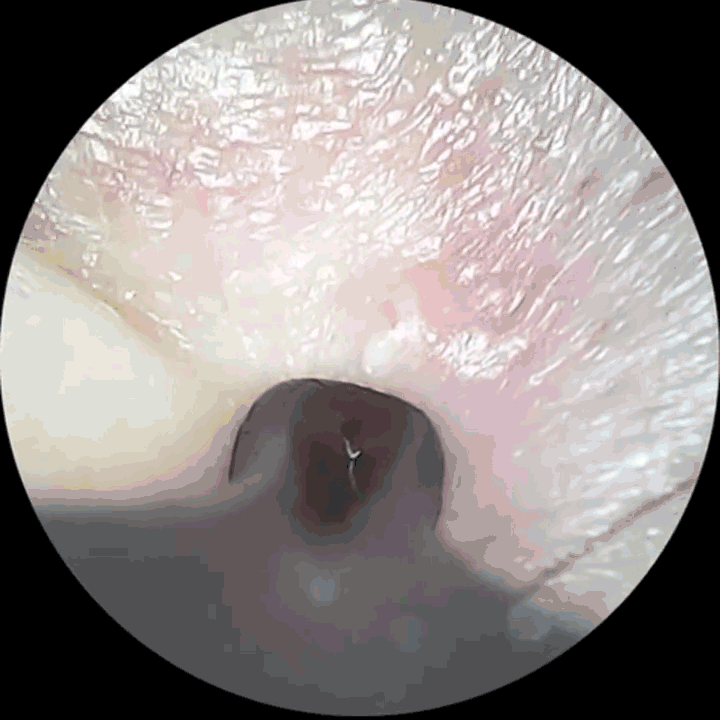

(图源文献3)皮肤镜下可看到嵌入的毛发。

(图源文献2)也可能长出皮肤表面后再进入皮肤内。(外面不好混,毛毛想回家了)

(图源文献3)在皮肤表面可以看到毛发从毛囊口露出再进入皮肤形成的圈。